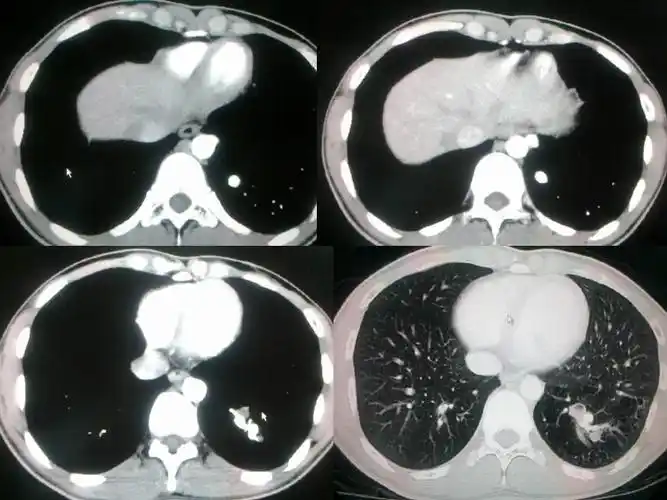

肺隔离症影像表现

肺隔离症影像表现_郑孝飞